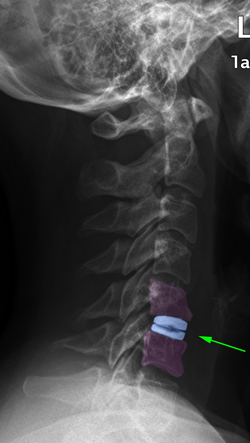

Αυχενικές δισκεκτομές με αρθροπλαστική (αριστερά), σπονδυλοδεσία με κλωβό (μέσο), σπονδυλοδεσία με κλωβούς πλάκα και βίδες.